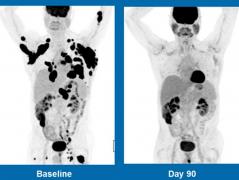

PREMIERĂ URIAŞĂ! Pacienţi aflaţi în fază terminală de CANCER, vindecaţi printr-o TERAPIE REVOLUŢIONARĂ: "Datele sunt fără precedent!"

O companie privată de medicamente a dezvoltat o terapie experimentală împotriva cancerului care a dat "rezultate extraordinare".

Bolnav de cancer de prostată în fază terminală, vindecat printr-un nou tratament experimental. Rezultatele i-au susprins chiar şi pe cercetători

Un bolnav de cancer de prostată a fost vindecat în urma unui nou tratament experimental, pus la punct de cercetătorii de la...